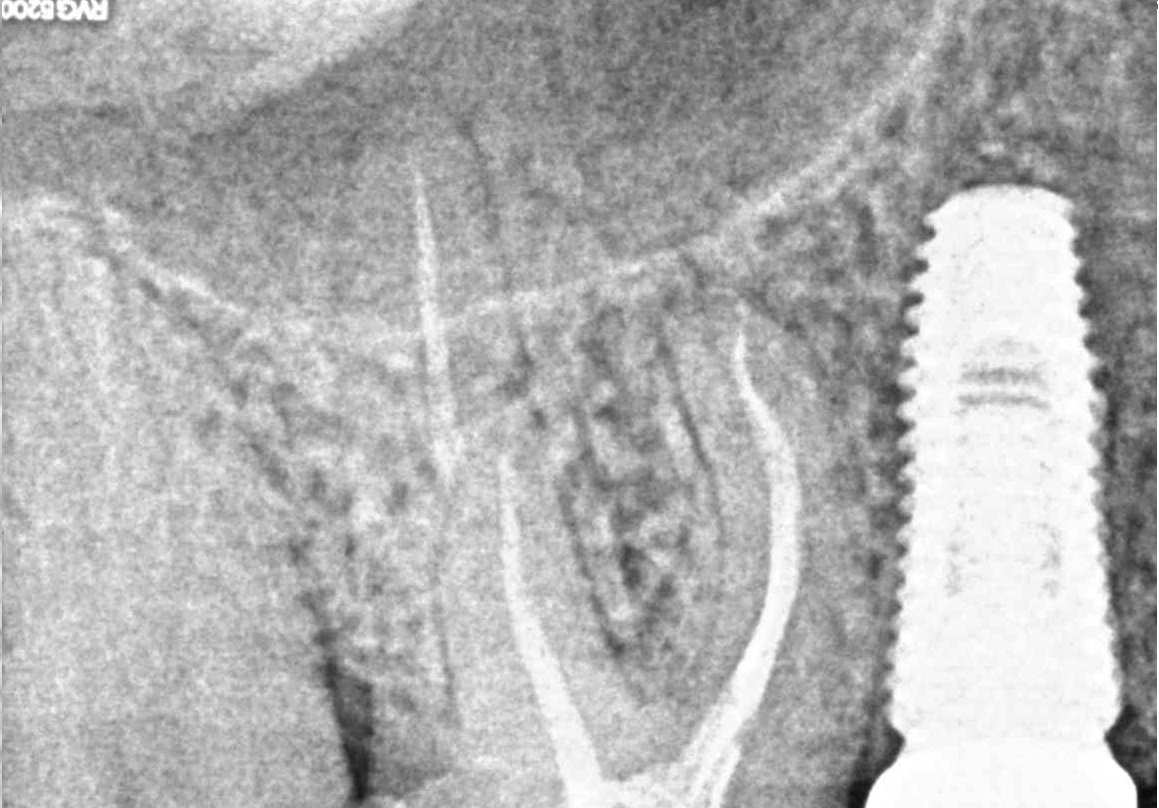

Перелечивание эндодонтически пролеченных зубов. Екатеринбург, 2014 г.

Современные протоколы эндодонтического лечения от диагностики до обтурации. Москва, 2021г.

Лечение пульпитов и периодонтитов. Пошаговые протоколы. Stom-Academy, 2022г.

Лечение кариеса, пульпита, периодонтита.